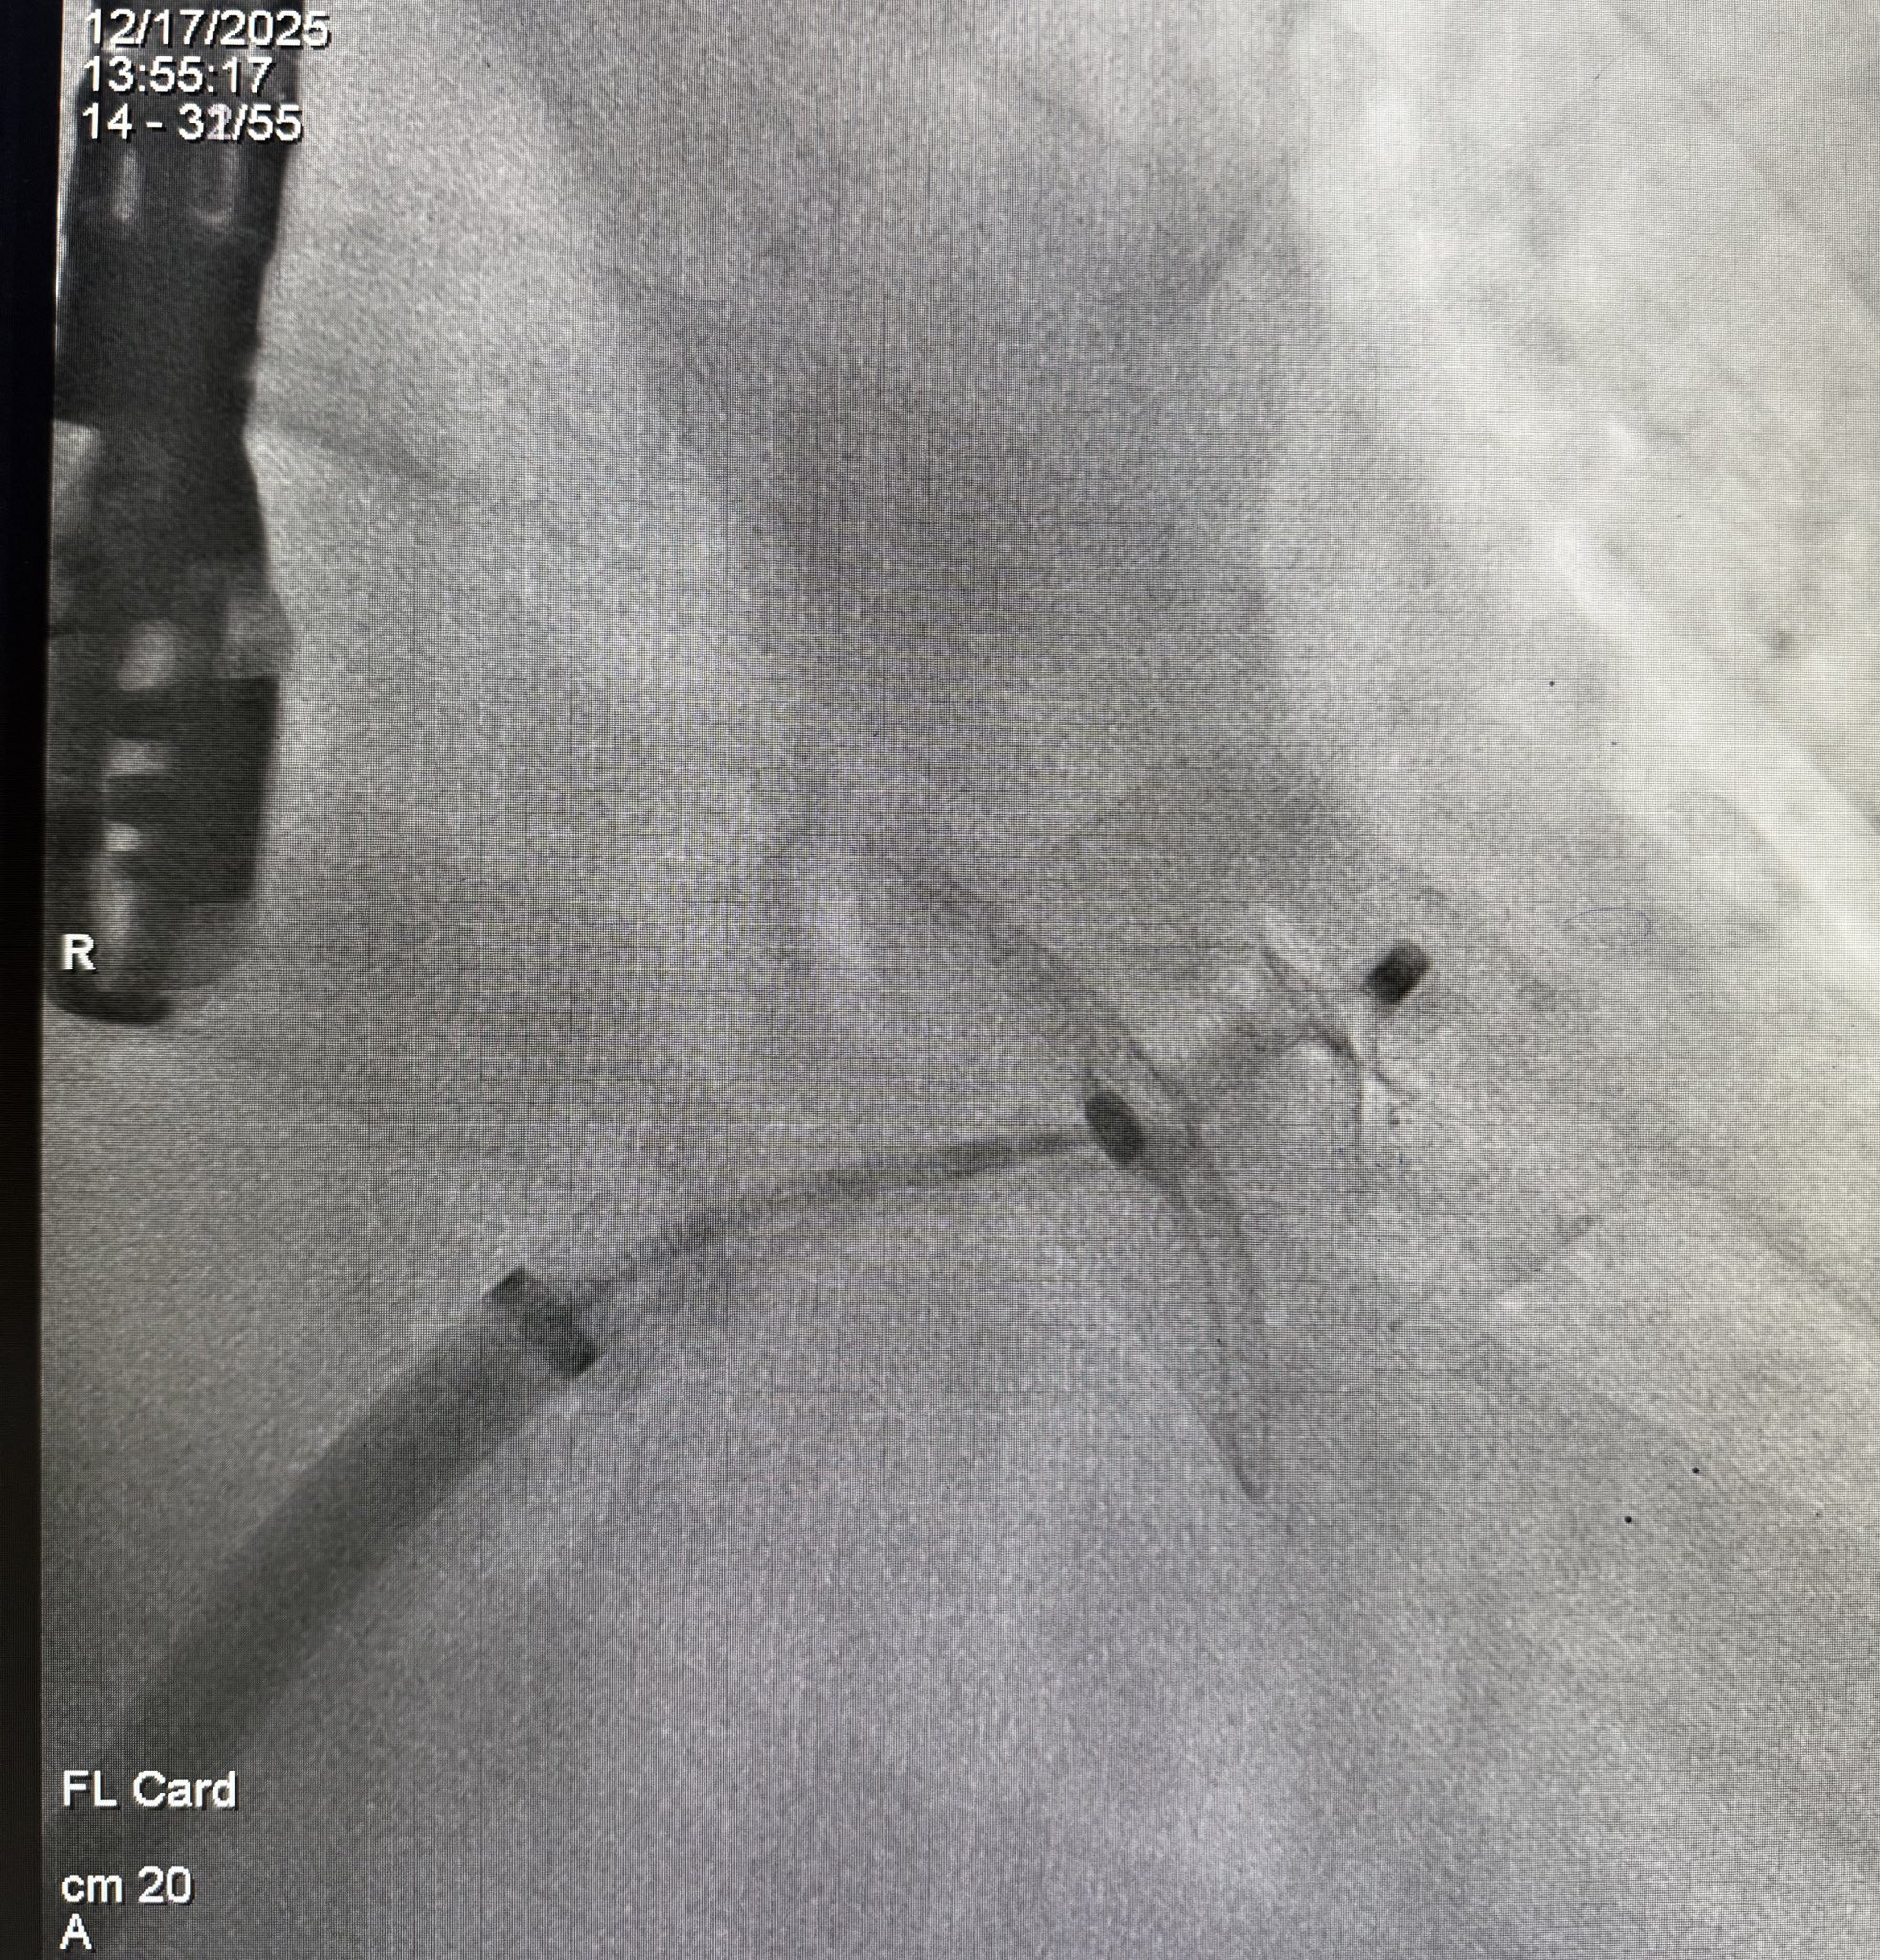

Kan sulandırıcı tedavi kullanmasına rağmen felç geçiren ve kalpten kaynaklı pıhtı riski yüksek olan bir hastada, ameliyatsız ve anjiyografik yöntemle “Sol Atriyal Appendiks Kapama” işlemi başarıyla gerçekleştirildi. İşlem, açık cerrahiye gerek duyulmadan, damar yoluyla ilerletilen özel bir oklüzör cihaz aracılığıyla uygulandı.

Sol atriyal appendiks kapama işlemi; non-valvüler atriyal fibrilasyon hastalarında pıhtıların en sık oluştuğu bölge olan sol atriyal appendiksin, perkütan yöntemle kapatılması esasına dayanıyor. Bu sayede pıhtının beyne gitme riski büyük ölçüde azaltılıyor.